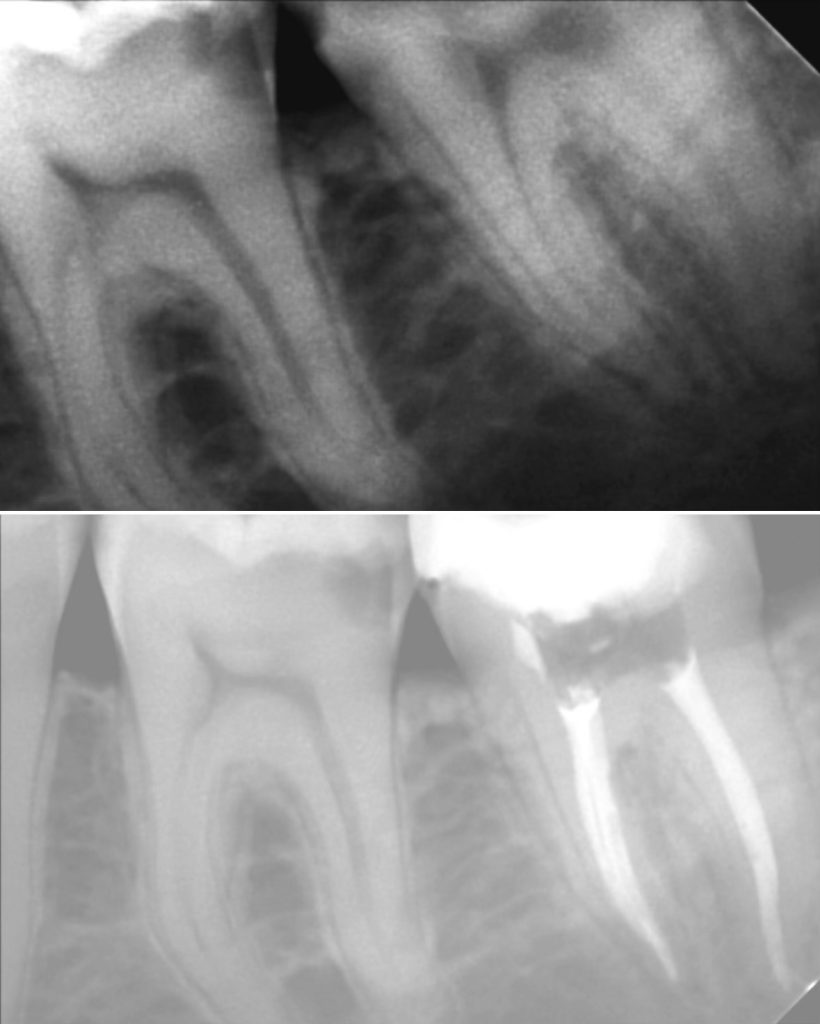

• Диагностика и лечение кариеса и его осложнений (пульпиты, периодонтиты)

• Эндодонтическое лечение корневых каналов с использованием стоматологического микроскопа